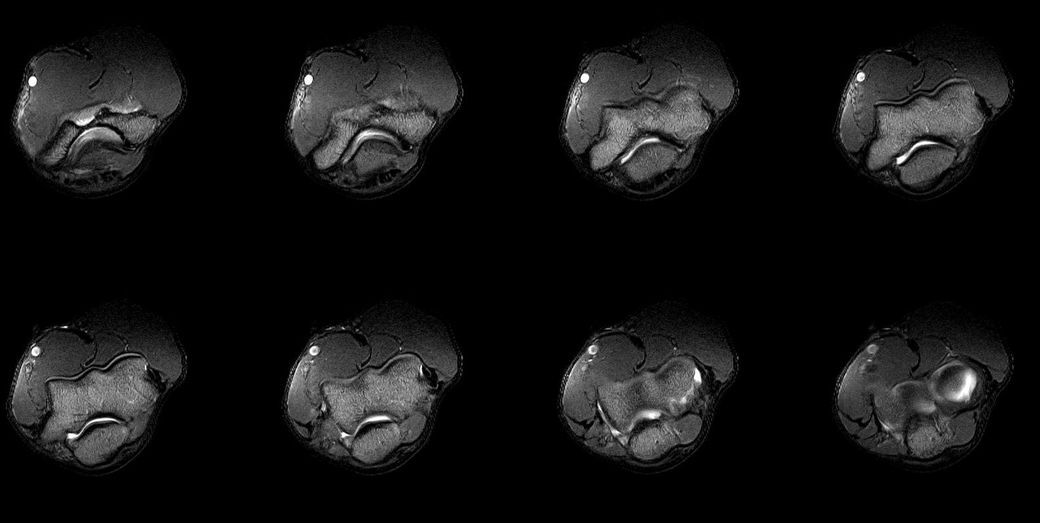

검사 결과 (7월 중순)

- MRI: 좌측 삼두건 경미한 염증, ulnar nerve supracondylar level 경미한 신호 증가

- 초음파/근전도: 척골신경 아탈구 확인

아래는 관련 사진 첨부합니다.

• 2번 째 사진